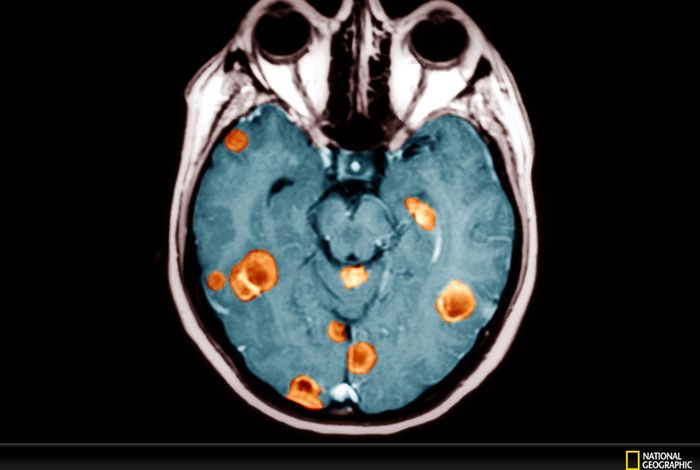

Single-workflow nanopore whole-genome sequencing with adaptive sampling for accelerated and comprehensive paediatric cancer profiling

ROBIN: A unified nanopore-based assay integrating intraoperative methylome classification and next-day comprehensive profiling for ultra-rapid tumour

Real-time genomic characterisation of paediatric acute leukaemia using adaptive sampling